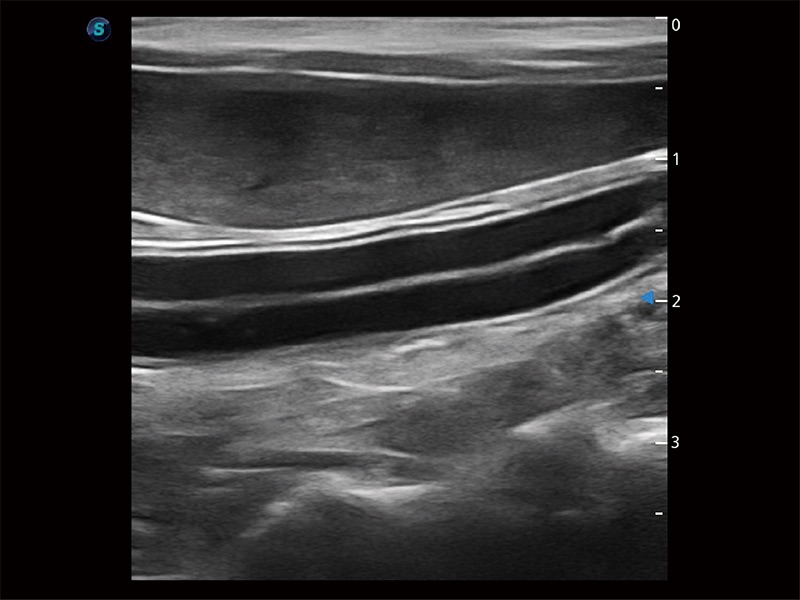

高性能和先進(jìn)的臨床應(yīng)用工具可以為動(dòng)物醫(yī)生提供臨床信心。ProPet 80 搭載了先進(jìn)的腹部和淺表應(yīng)用工具,幫助醫(yī)生在日常臨床實(shí)踐中發(fā)揮前所未有的作用。

極大提升超低速微細(xì)血流的檢出能力,同時(shí)更精準(zhǔn)地濾除軟組織和超聲信號(hào),為獸用醫(yī)生提供以往無(wú)法通過(guò)常規(guī)血流獲得的疾病診斷信息。

操作簡(jiǎn)便,無(wú)需高頻度外力作用即可真實(shí)反映組織的形變,快速評(píng)估腫瘤良惡性。